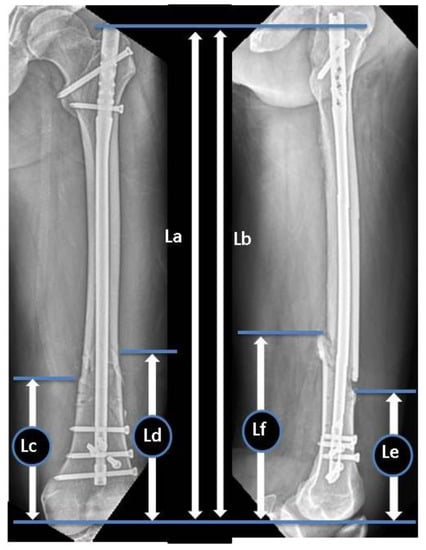

During the study period, eight parameters were measured in the anteroposterior (AP) and lateral views of preoperative and immediate postoperative radiographs to evaluate the radiographic risk factors for non-union. Preoperative radiographs were evaluated to classify the fracture types in accordance with the AO Foundation/Orthopaedic Trauma Association (AO/OTA) classification system [16]. Goniometric measurements were performed using immediate postoperative radiographs to determine the coronal plane angulation on AP radiographs and the sagittal plane angulation on lateral radiographs (the long axes of the proximal and distal fragment’s diaphyses intersect). The ratio of the distal fragment was measured using immediate postoperative radiographs in accordance with the protocol by Watanabe et al. (Figure 1). The ratio of the unfixed distal segment, as well as the ratio of IM canal diameter to nail size at the level of fracture (C/N ratio) (Figure 2), and the number of distal locking screws and poller screws were also measured.

Figure 2.

Ratio of the unfixed distal segment: A/B. A: Distance from the tip of the nail to the intercondylar notch in the AP view, B: main distal fragment length from the proximal fracture line to the intercondylar notch in the AP view. Ratio of the IM canal diameter to nail size at the level of fracture: C/N. C: IM canal diameter at the level of fracture in the AP view, N: nail size in the AP view.